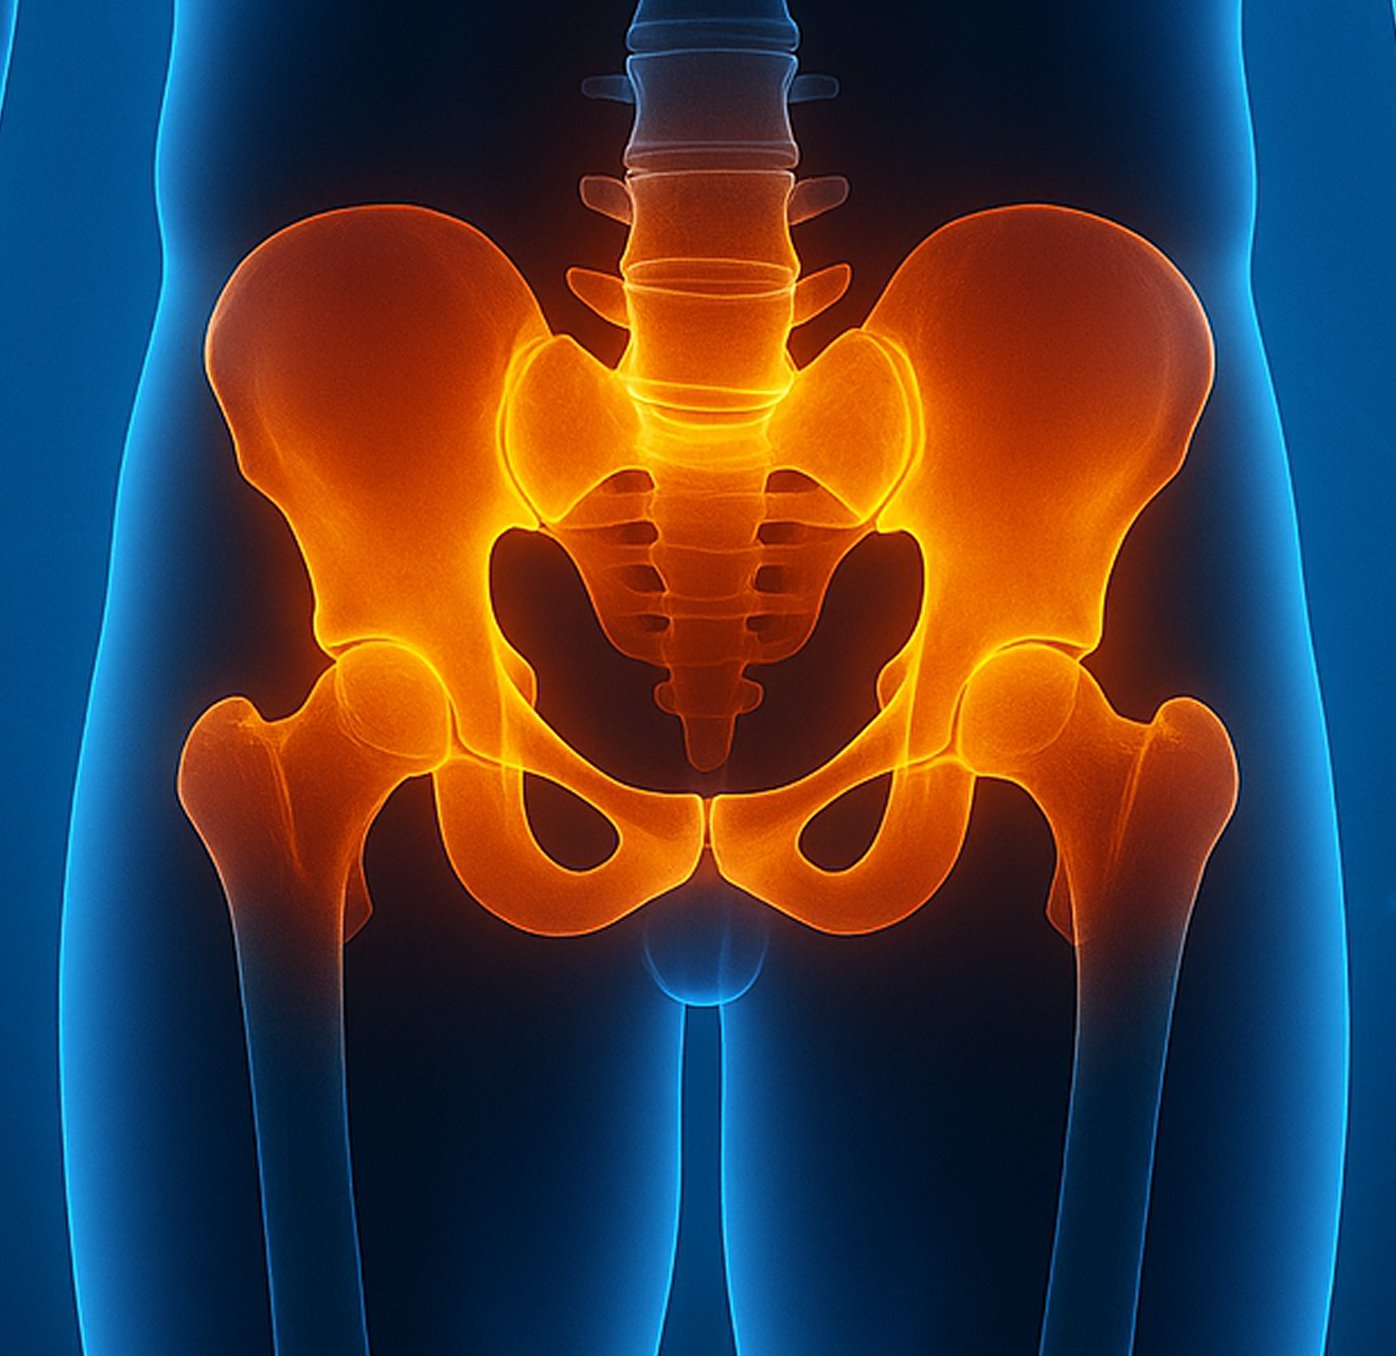

Pelvic reconstruction surgery addresses damage or instability in the pelvic region, restoring function and reducing pain for those affected by trauma, congenital abnormalities, or degenerative conditions. The pelvis supports essential movements and stability, and any disruption can severely limit daily activities. At Valiant Clinic, we understand how these issues affect your comfort and independence, and we’re dedicated to helping you regain stability and mobility with advanced pelvic reconstruction procedures.

How Our Pelvic Reconstruction Surgery Works

Pelvic reconstruction at Valiant Clinic uses a detailed, patient-focused approach. We assess how the injury or condition affects your life and create a comprehensive surgical plan that combines advanced techniques, rehabilitation, and supportive care.